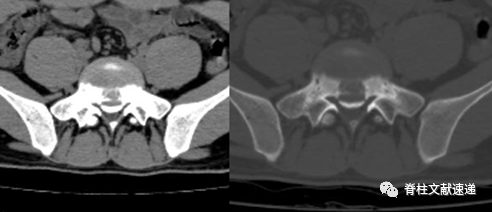

上图是Takata早期提出的分型。

上图为笔者临床所见病例资料,与A型相近。